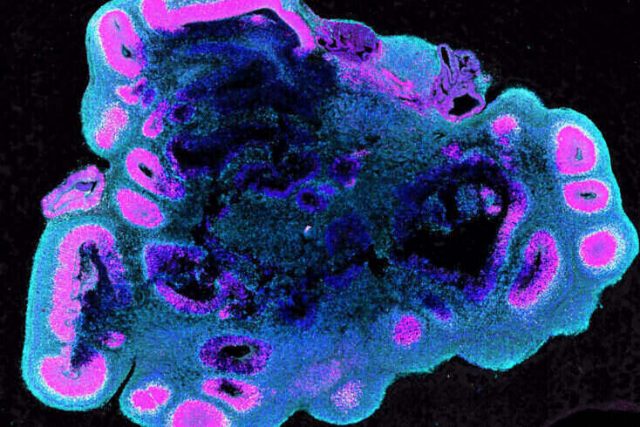

Ilmuwan Menemukan Saklar Molekuler yang Membuat Otak Manusia Menjadi Besar

Apa yang membuat manusia berbeda dengan primata lainnya, salah satunya adalah volume otak yang lebih besar. Sebuah studi untuk pertama kalinya mengidentifikasi bagaimana pertumbuhan otak manusia bisa berkembang jauh lebih besar, dibandingkan dengan otak simpanse dan gorila. Dalam pengamatannya, para peneliti menggunakan otak organoid. Yaitu, suatu versi miniatur dan disederhanakan dari organ tubuh. Diproduksi di laboratorium dari sel punca (sel...